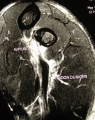

La rupture basse du biceps est beaucoup moins fréquence que celle de sa longue portion proximale et son traitement en est totalement différent. Elle touche volontiers l'homme de la quatrième décade avec un sur-risque chez le fumeur. Le traitement non chirurgical ne donne pas un bon résultat sur la force de flexion et de supination de l'avant-bras avec une relative fatigabilité de ces gestes. Néanmoins, la chirurgie ouverte "classique" nécessite une longue incision sinueuse antérieure et inesthétique et le taux de complications -notamment nerveuses- est relativement élevé.

Nous avons décrit une technique endoscopique mini-invasive que nous avons publiée dans l'American Journal of Sports Medicine. Elle s'avère sûre et reproductible dans ses résultats avec un taux plus faible de complications. C'est notre technique de choix de réparation de ces lésions du biceps, notamment chez le sportif de haut niveau comme les rugbymen.